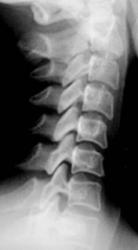

Иллюстрации 1, 2, 3. Определяется «выпрямленность» шейного лордоза, неравномерное сужение межпозвонковых щелей в сегментах С2-С3, С3-С4. Резкое сужение межпозвонковых щелей в сегментах С4-С5, С5-С6, С6-С7, с выраженным субхондральным склерозом тел позвонков, неровностью замыкательных пластинок, образованием остроконечных остеофитов по передней поверхности тел позвонков. В дугоотросчатых суставах определяется сужение суставных щелей с выраженным субхондральным склерозом. На иллюстрации 2 хорошо дифференцируется остеосклеротическая перестройка тел С4, С5, С6, С7, как компенсаторная приспособительная реакция, в результате анатомической и функциональной несостоятельности межпозвонковых дисков.